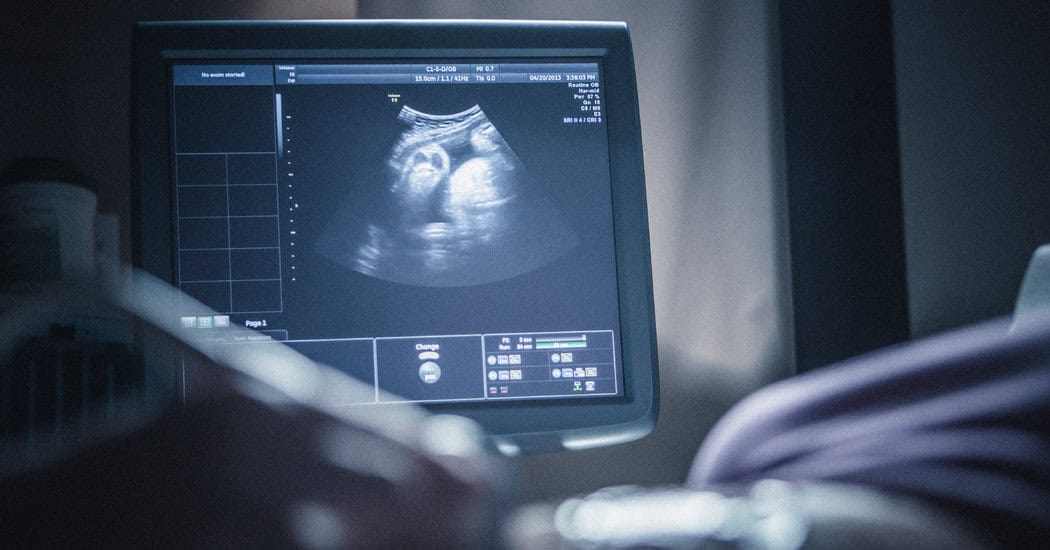

An ultrasound scan uses high-frequency sound waves to create images of structures inside the body. These sound waves are transmitted through a handheld device called a transducer, which captures real-time images that help healthcare providers evaluate organs, tissues, and blood flow. Because ultrasound does not involve radiation, it is widely used for many diagnostic purposes.

During the exam, you will be asked to lie comfortably on an exam table. A small amount of gel is applied to the skin over the area being examined. This gel helps the transducer move smoothly and allows sound waves to travel effectively.

The ultrasound professional will gently move the transducer across the skin to capture images. You may be asked to change positions or hold your breath briefly to help obtain clearer views. For those asking what to expect during an ultrasound scan, most patients describe the experience as quiet, calm, and painless.